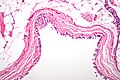

Lung parenchyma (left) and bronchial epithelium (right) on a biopsy. H&E stain. (WC)

Bronchial mucosa

• Ciliated pseudostratified epithelium.

• Minimal/mild inflammation.

Lung parenchyma

Common:

• Type I pneumocyte - cover most of the alveolar surface.

• Type II pneumocyte - stem cell, produce surfactant.

• Typical location: "angle of alveolus".

• Macrophages.